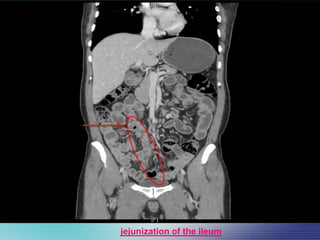

Pt underwent CT scan of the abdomen

• Work up :

jejunization of the ileum

 CT abdomen and pelvis with IV contrast

FINDINGS :

Multiple mesenteric lymphadenopathies

, largest one measuring 1.7cm.

Mild hepatomegaly.